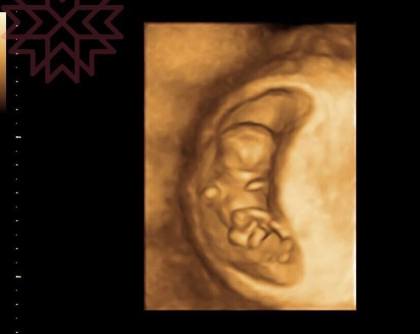

今天這張也這是我隨機在門診抓的3D圖

在3D下

胚囊是正圓的嗎

不是吧?

說實話

如果我真的故意要玩你

我可以搞出各式各樣的變化

在2D下切出各種形狀

其實我要說的是

用單一切面超音波的圖像來判斷其實並不保險

因為妊娠囊是立體的